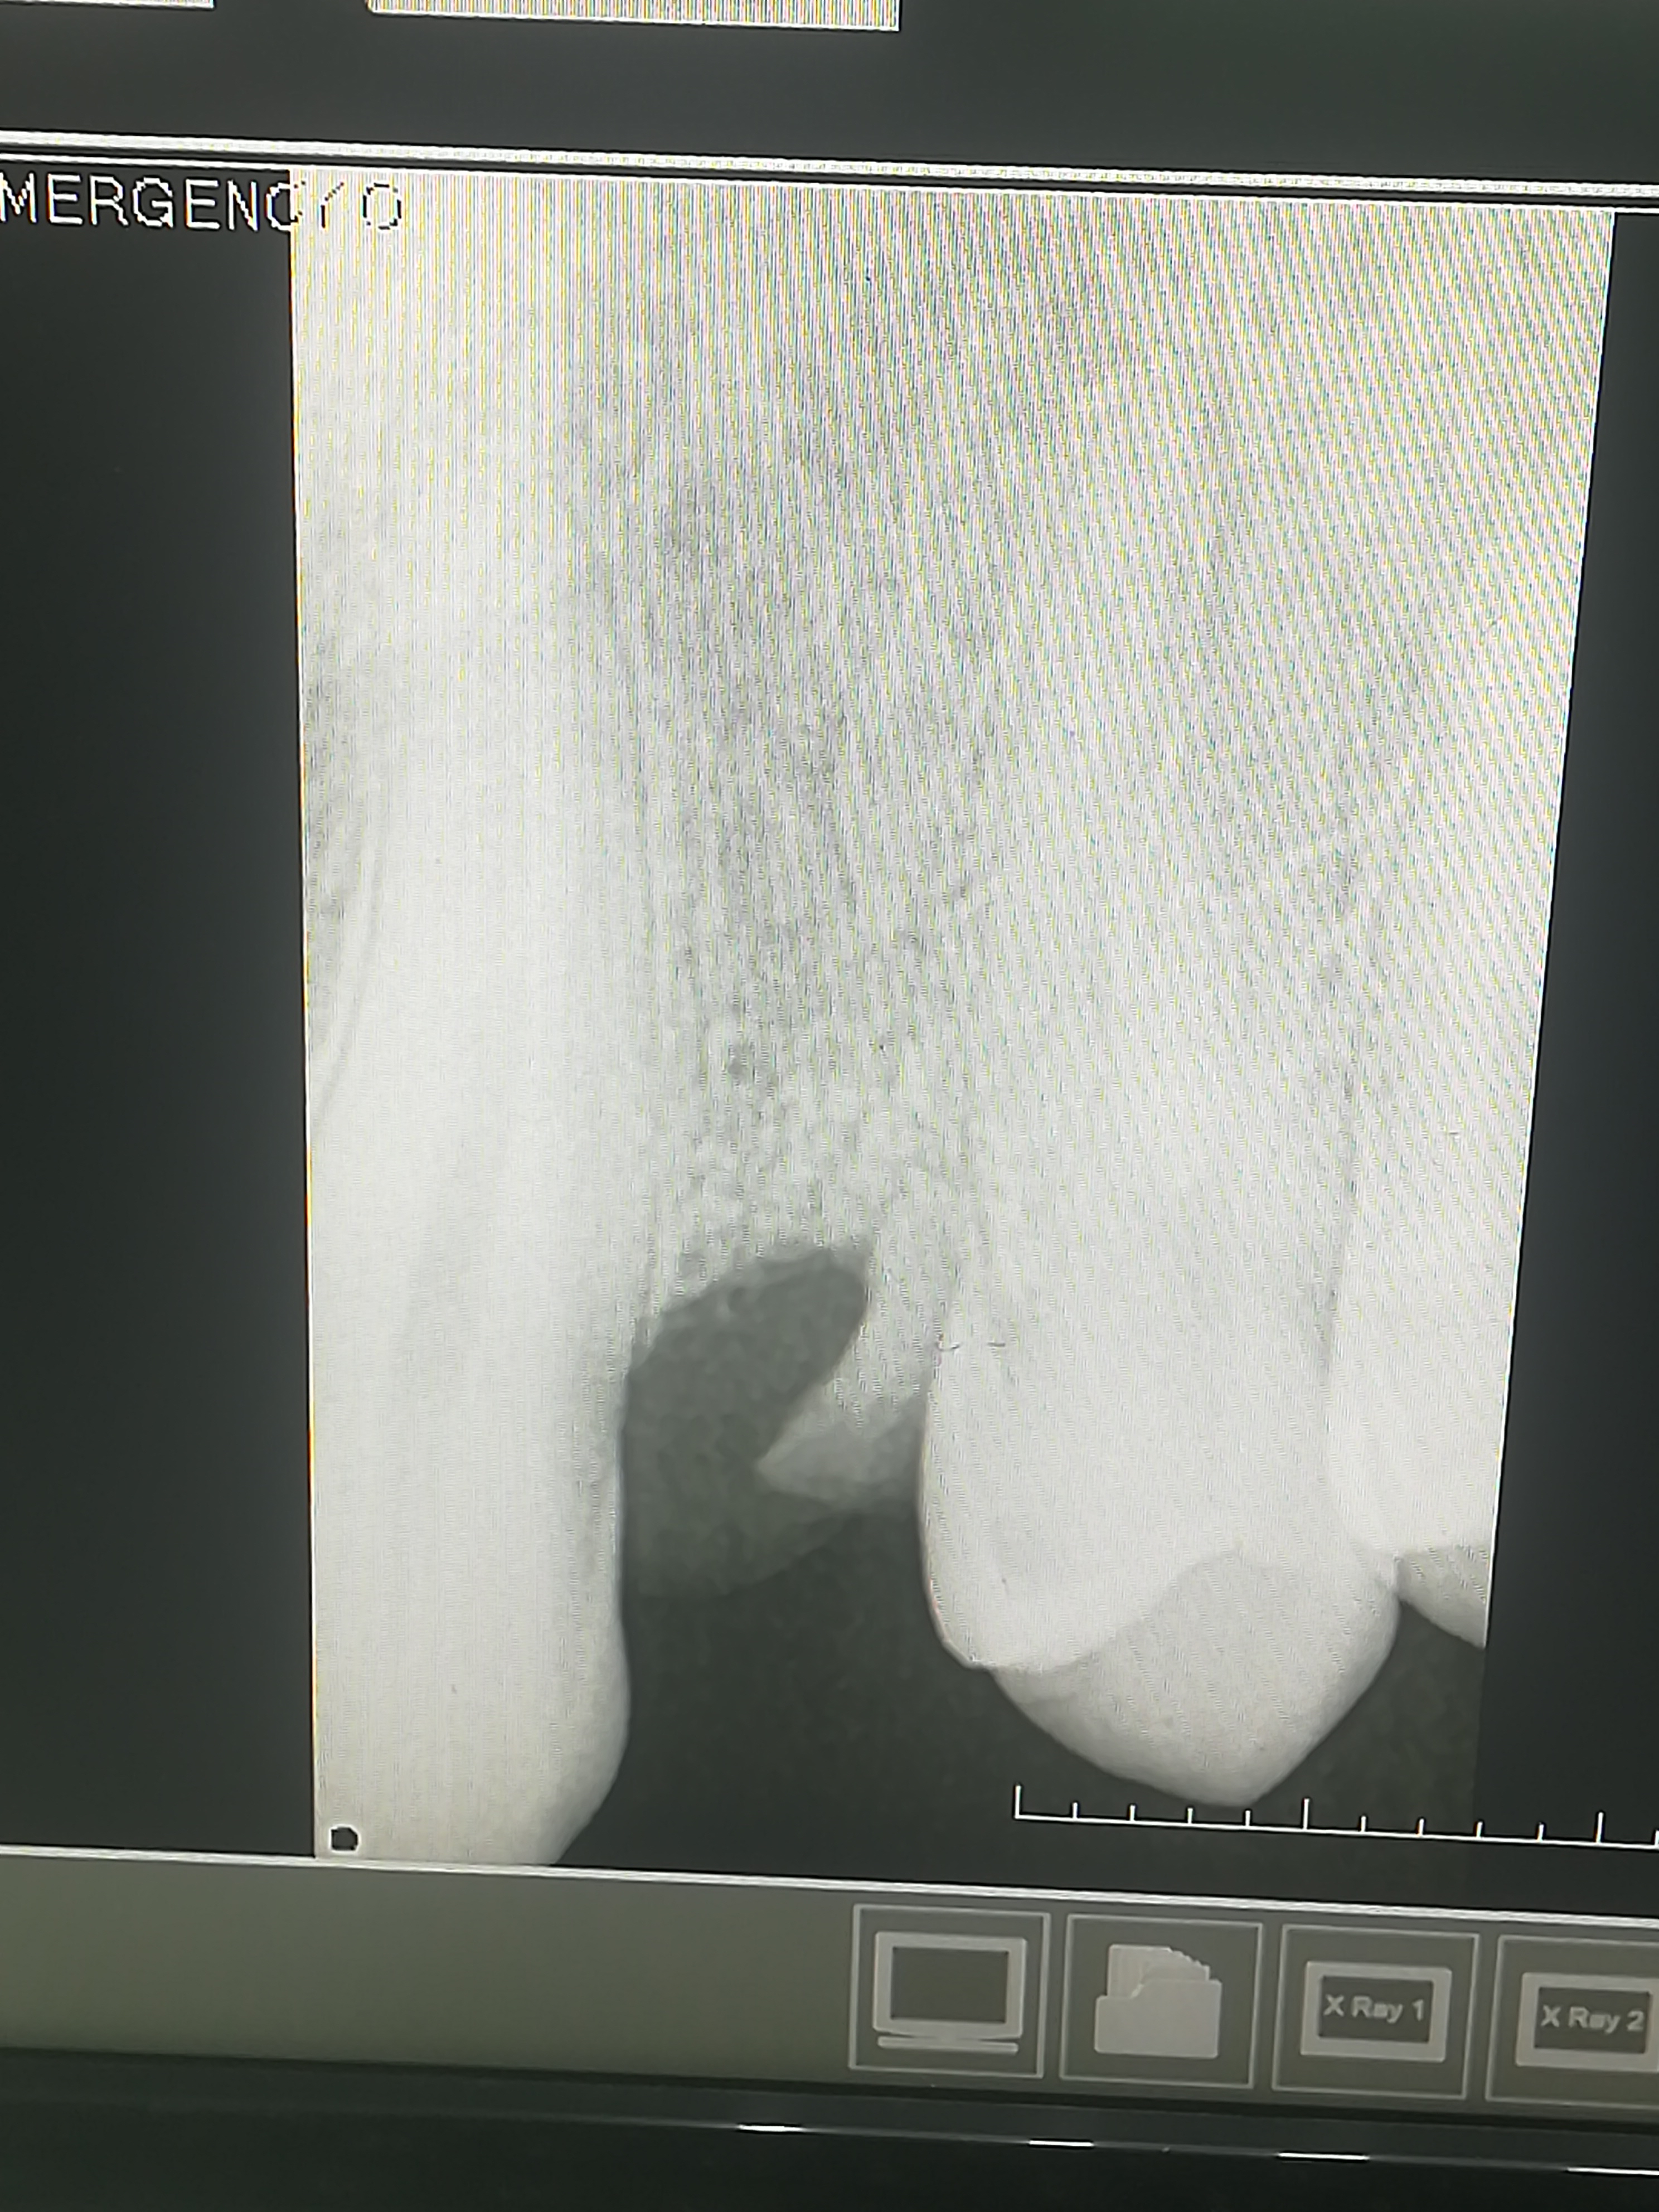

1000070960.jpg 313Кб, 1117x832

1117x832

1000070961.jpg 180Кб, 882x704

882x704

Зуб пятерка. Возможно такое вылечить, анонче? Отклолся как то, вообще не болит.